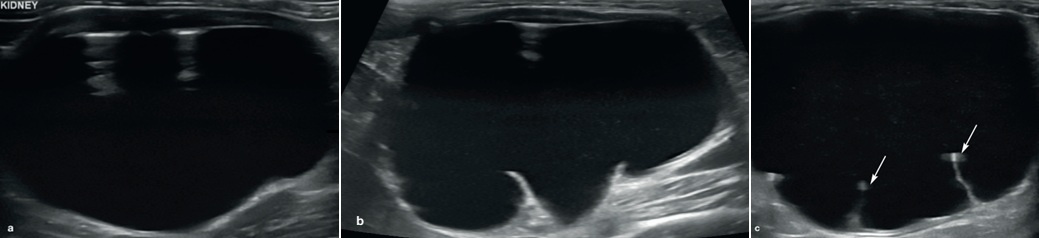

요의 정체(urinary stasis)와 그에 따른 감염은 농신증(pyonephrosis)으로 이어질 수 있습니다. 농신증은 문자 그대로 신우 안의 고름을 의미하며, 고양이에서 요관결석(ureterolithiasis)이 있는 경우 및 대정맥후 요관(circumcaval ureter; 선천성 기형으로 요관이 후대정맥의 뒤쪽으로 감겨들어 간 상태)이 있었던 단일 증례에서 보고된 바 있습니다.

초음파 소견으로는 신우 내 고에코성 잔사(찌꺼기), 수신증, 정상 신장 구조 소실 등이 포함됩니다(그림 4).